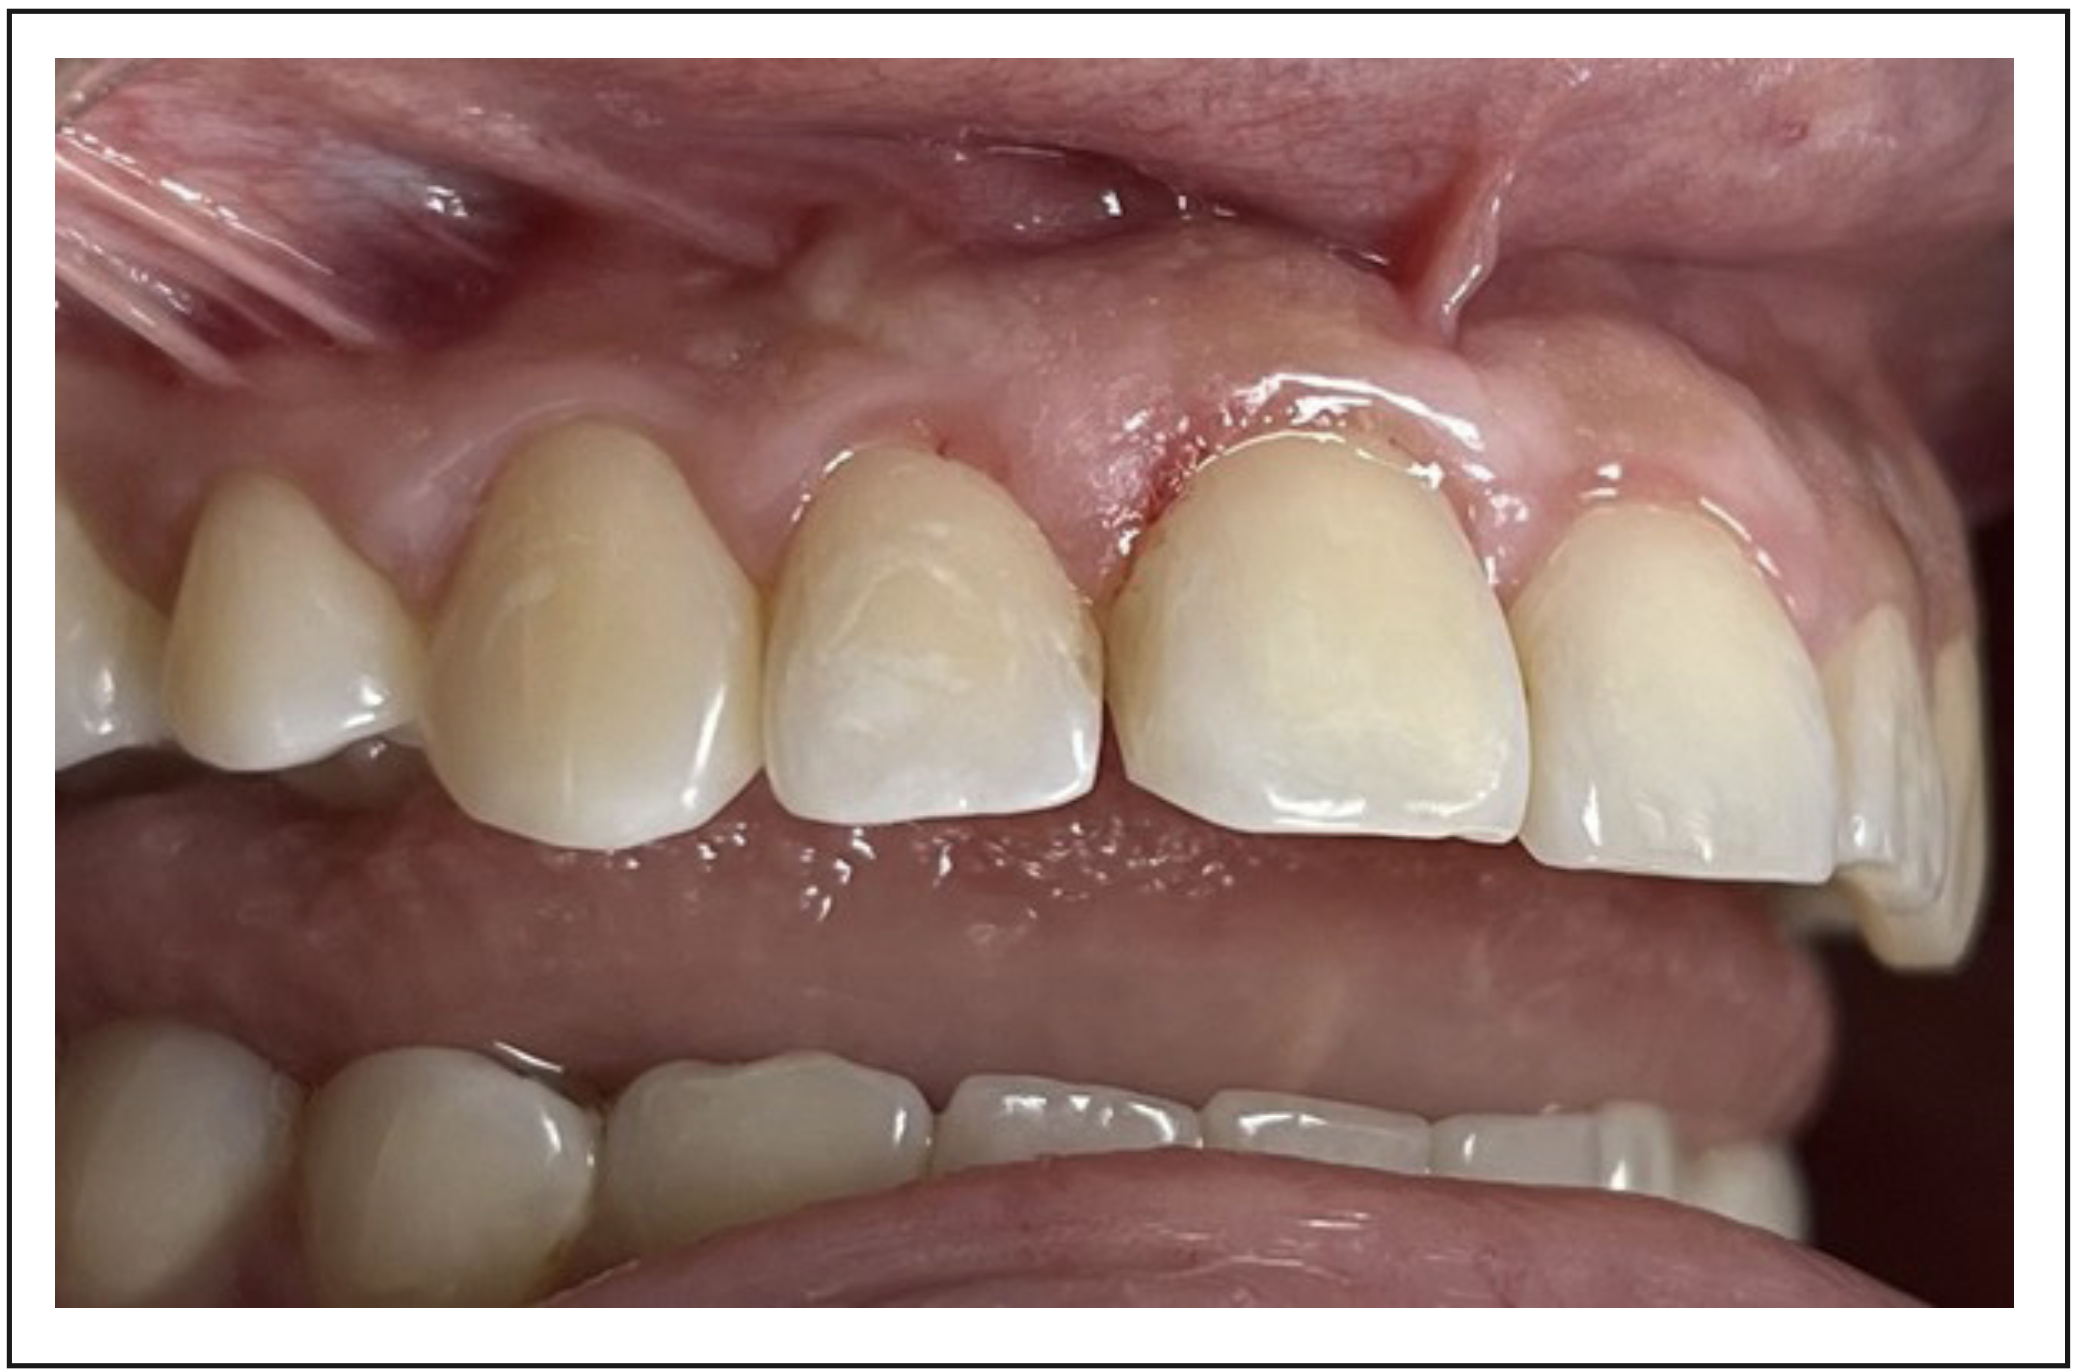

El primer control fue realizado a los 7 días, retirando las suturas y controlando la evolución. La paciente relató ligeras molestias en la descarga vertical, ligero aumento de volumen y ausencia de dolor. En esta sesión se realizó la remoción del sellado provisorio, se eliminó el exceso de gutapercha cameral y se efectuó el sellado coronario definitivo con resina compuesta (Filtek® z350, 3M, Minnesota, Estados Unidos) en la cara palatina.

Se controló al mes (Figura 5), momento en el que se recibe el resultado de la biopsia indicando la presencia de un granuloma.

Figura 5. Control al mes posterior a la microcirugía apical donde se observa una evolución positiva respecto a la cicatrización de los tejidos. La paciente relata una mejora notable y ausencia de dolor en la zona de descarga vertical.

Posteriormente, se controló a los 3, 6 y 12 meses observando una excelente evolución en el tiempo: ausencia de signos o síntomas compatibles con inflamación o infección tanto clínica como radiográficamente, siendo la ausencia de movilidad uno de los factores de bienestar más importantes para la paciente. En la tomografía de haz cónico del control anual observamos la recuperación de la tabla vestibular y el relleno óseo del defecto observado anteriormente (Figura 6 y 7).

Figura 6. Control al mes posterior a la microcirugía apical donde se observa una evolución positiva respecto a la cicatrización de los tejidos. La paciente relata una mejora notable y ausencia de dolor en la zona de descarga vertical.